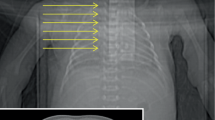

Diagnostic PMCT and lung abnormalities

Seventy-five percent (9/12) of examinations were judged non-diagnostic (typically a ‘white-out’) prior to ventilation, compared to 100 % (12/12) judged diagnostic following ventilation (p < 0.005; Fig. 3). We were unable to distinguish between normal and abnormal lung areas on the basis of HU on the conventional PMCT images as most were non-diagnostic. Seven patients had lung parenchymal abnormalities identified on vPMCT images, although only four of these had these abnormalities confirmed at autopsy. On pre-vPMCT images, mean HU for normal lungs (−134.1 ± 215.1) were lower (more aerated) but not significantly different from abnormal lungs (−45.3 ± 135.2; p = 0.22; Fig. 4). We did not find a relationship between postmortem interval and lung opacification nor an effect on ventilation, although our range of postmortem interval values was narrow (Table 1).

Effect of ventilation on abnormal lung areas

Seven patients had areas of lung abnormalities identified on vPMCT. Mean abnormal lung HU did not change significantly with ventilation (pre-vPMCT −45.3 ± 135.2 vs post-PEEP vPMCT −70.5 ± 164.5; p = 0.70; Fig. 4; Table 1). In two cases, lung consolidation or collapse was identified on vPMCT but not confirmed at autopsy; in one case, this may have been due to a sampling error as the lingula was not sampled at autopsy (Fig. 5; case 9). In one other case, patchy consolidation was identified in a child who also developed a pneumothorax following vPMCT, which may have led to under-aeration of the lungs and a false positive diagnosis. All five cases in which the vPMCT appearances were normal were confirmed as normal at autopsy. Preliminary sensitivity and specificity of vPMCT were 100 % (95 % CI 51.5, 100) and 62.5 % respectively (95 % CI 30.6, 86.2; Table 2). The negative predictive value was 100 % (95 % CI 56.5, 100).